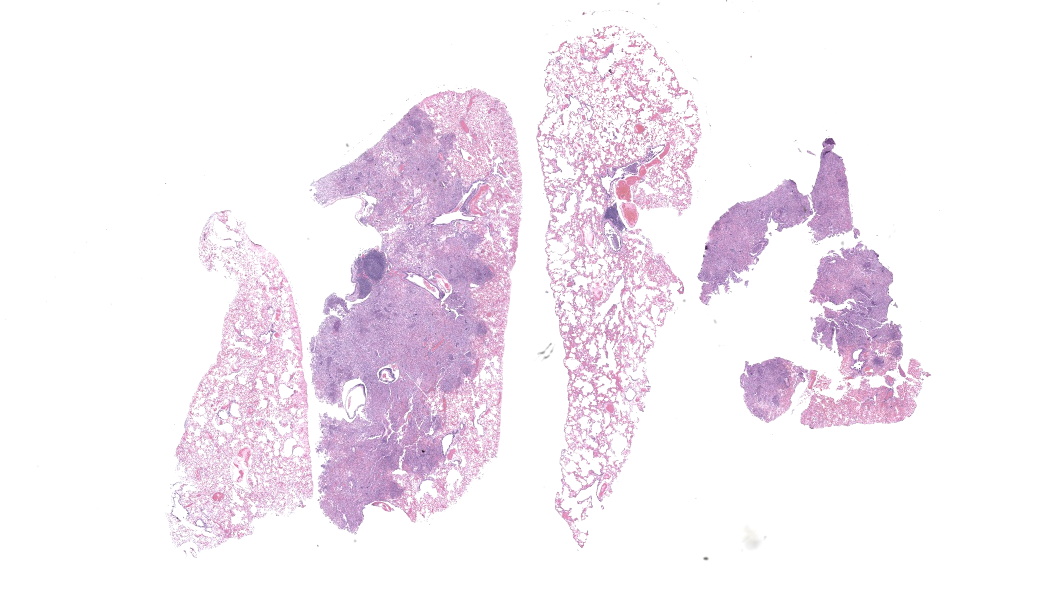

Prairie dog sourced from a zoologic collection. Clinical presentation for acute ptyalism, easily captured, poor vision. Clinical examination noted superficial healing wounds on bilateral forearms, facial scarring with intermittent swellings, incisor malocclusion, elongate buccal aspects of mandibular molars, bilateral tongue ulceration.Gross Pathology:

External examination of the lungs was normal. On serial sectioning and trimming in representative sections of lung a single small sample of lung tissue was noted as floating low in formalin solution; on examination of one aspect of the cut section the lung was pale tan and consolidated with multifocal pale tan, circular, soft foci (exudate filling bronchi). The total volume of affected lung mass was less than 10%.Laboratory Results:

Lung, multiple sections. Within a single section of lung, approximately 75% of the bronchial, bronchiolar, and alveolar lumina contain overall large numbers of neutrophils, macrophages, large multinucleated cells, cellular debris, homogenous eosinophilic material, fibrillary eosinophilic material, and occasionally scattered erythrocytes. The multinucleated cells are often large and bizarre in appearance, some containing approximately 40 nuclei. The cytoplasm of these multinucleated cells is eosinophilic and variably granular to homogenous. A subset of these multinucleated cells contains few distinct optically clear vacuoles, while others demonstrate phagocytosis of few neutrophils. There is mild vascular congestion throughout, and there are small clusters of lymphocytes cuffing airways multifocally.Contributor's Morphologic Diagnoses: